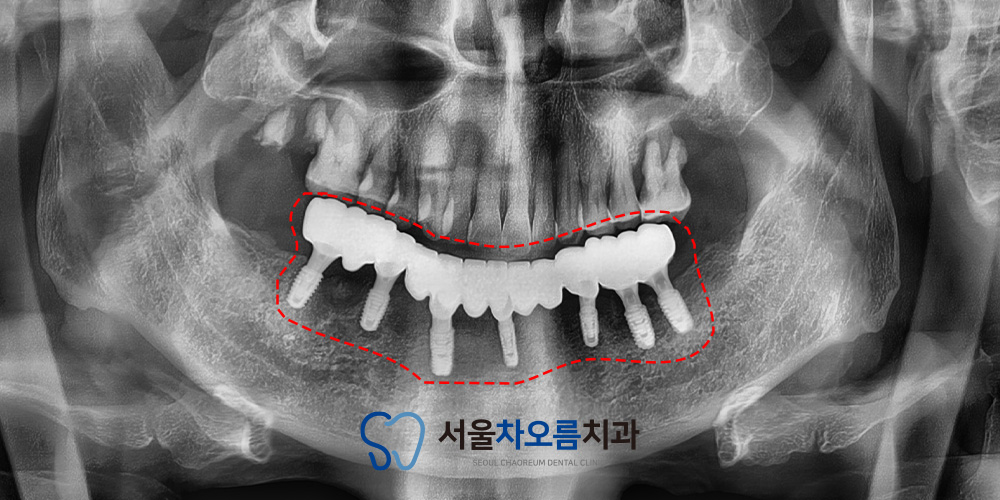

25.07.06

이후 임플란트의 수치를 재보니

이상 없이 잘 나오고 있었고,

그에 따라 최종 보철 작업을

시작하게 되었습니다.

최종 보철 작업을 진행하기 전,

치아의 높이나 맞물리는 부분을 확인하기 위해

왁스림을 진행하여 치아의

모양과 기능을 세밀하게 확인한 후,

정밀한 맞춤형 보철을 완성하였습니다.

25.03.21 / 25.07.06

치료 전후 사진입니다.